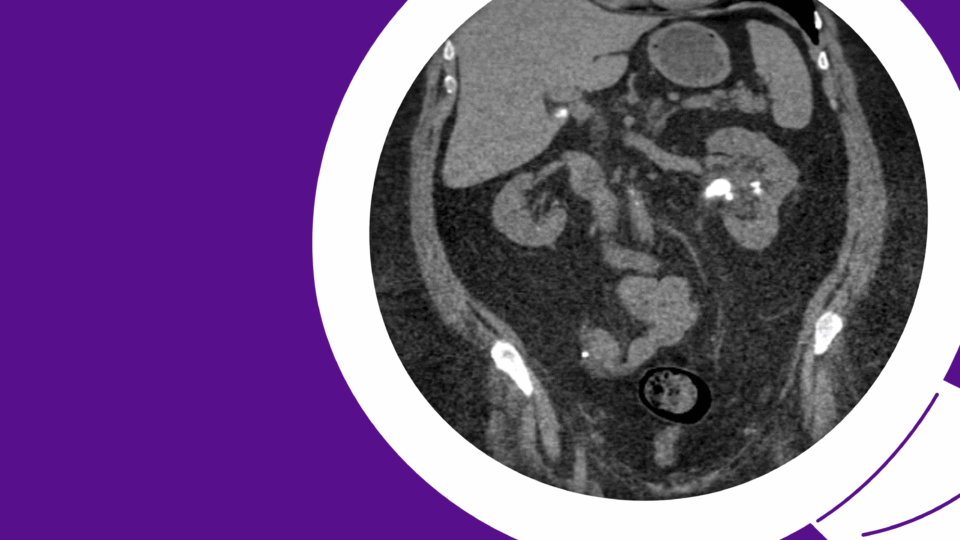

CT Scan Showing Carcinoma

The third case involved a 59-year-old man with a history of cardiovascular conditions, including coronary artery disease, severe aortic regurgitation, a cerebrovascular accident, and a thoracic aortic aneurysm repair. He had a biopsy-proven, enlarging solid 2.2 centimeter papillary renal cell carcinoma (red circle). PHOTO: NYU Langone Staff